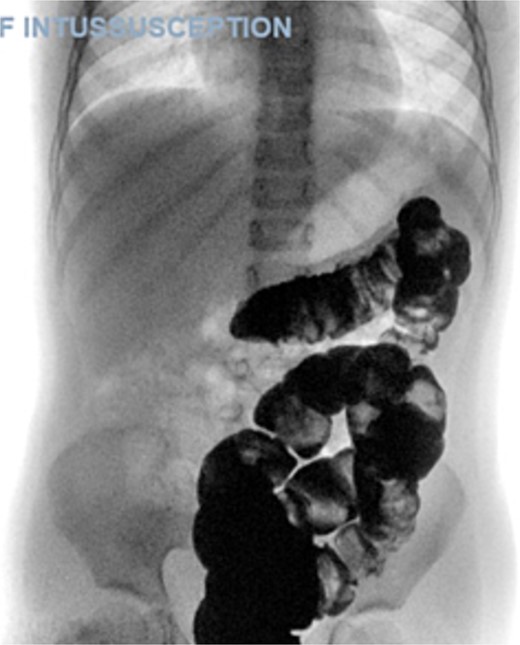

A 5-year-old female presented with a 1-day history of abdominal pain and vomiting. Physical examination revealed abdominal tenderness on the right side. The patient had a history of four previous episodes of intussusception, all of which were conservatively reduced with hydrostatic contrast enema (Fig. 1). The most recent episode occurred 3 months prior to the current presentation. An MRI enterography performed after the fourth episode showed no abnormalities.

Ultrasound of the abdomen showed a target sign of intussusception (5th attack).